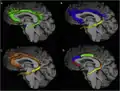

One way to subdivide the cingulum. In this animation, the cingulum is divided into the five components. One way to subdivide the cingulum. In this animation, the cingulum is divided into the five components.

There are various ways to subdivide cingulum.[6] From figure A to D, dividing the cingulum into 1, 2, 3, and 5 components respectively. There are various ways to subdivide cingulum.[6] From figure A to D, dividing the cingulum into 1, 2, 3, and 5 components respectively.